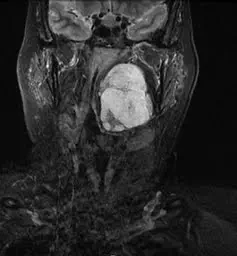

ש', בת 70 מאזור הצפון, חיה במשך 20 שנה עם גידול שפיר בראשה. הגידול, אשר ממוקם בין בסיס הגולגולת ללסת, קרוב לעין ולעורק הראשי המוליך למוח, התפתח לאורך השנים וגדל באיטיות.

לבסוף הגיע הגידול לממדים של אגס והיה כל כך גדול עד שגרם לה לחנק, להפרעות אכילה, לכאבים, ואפילו לסיכון חייה. הניתוח המקובל לכריתת גידול מסוג זה מצריך חתכים בצוואר ובפנים וניסור הלסת. משמעות ניתוח זה הוא אשפוז ארוך ופגיעה לא פשוטה באיכות החיים של המטופלת.

ש' פחדה לעבור ניתוח כה מורכב, והגיעה לקריה הרפואית רמב"ם, לצורך התייעצות עם פרופ' זיו גיל, מנהל המחלקה אא"ג וניתוחי ראש צוואר, שם הוצא לה פתרון מודרני לטיפול בבעיה שממנה היא סובלת - ניתוח זעיר פולשני בעזרת רובוט. לפני כשבועיים, עברה ש' ניתוח ייחודי, ראשון מסוגו בארץ ומהראשונים בעולם, להסרה של הגידול מראשה - בעזרת רובוט ה"דה וינצ'י". הניתוח בוצע כולו דרך הפה, ללא צורך בביצוע חתכים בפנים וניסור הגולגולת.

בניתוח שנמשך 4 שעות וחצי, החדירו הרופאים, פרופ' זיו גיל, מנהל מחלקת אא"ג ניתוחי ראש צוואר ברמב"ם ודר' יקי כהן, מנהל מכון הקול והבליעה בביה"ח, שתי זרועות דקות בעובי 4 מ"מ כל אחת, לתוך הפה של החולה. כשהם נעזרים במצלמה תלת ממדית מזערית הצליחו הרופאים לבצע כריתה מלאה ומדויקת של הגידול, ללא צורך בביצוע חתכים בעור הפנים וללא צורך בניסור עצמות הראש. הגידול הוסר בשלמות, ללא פגיעה בעצבים או כלי דם שהיו בקרבת הגידול. כעבור 48 שעות לאחר הניתוח, החולה כבר החלה לשתות ולדבר בחופשיות ולא הזדקקה לטיפולים נוספים.